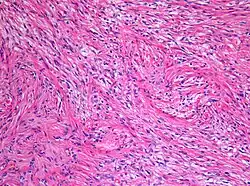

Gwiaździak włosowatokomórkowy (gąbczak, łac. astrocytoma pilocyticum, spongioblastoma, ang. pilocytic astrocytoma) – nowotworowy guz mózgu. Jest guzem o małej złośliwości (I° według WHO). Najczęściej lokalizuje się w półkulach mózgu, podwzgórzu, przednim odcinku drogi wzrokowej (glejak nerwu wzrokowego) i móżdżku. Postępowanie lecznicze zależy od umiejscowienia guza.